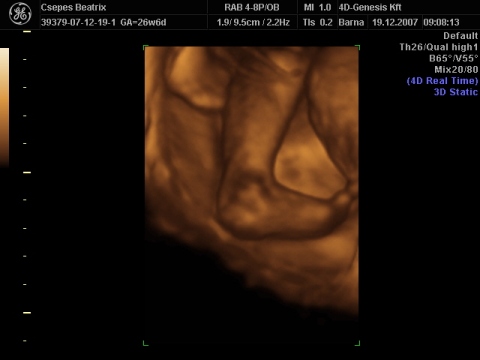

nálunk is 4Dn azt mondták, hogy kisebb a koránál picit, de legfeljebb nem születik nagy súllyal. szóval ez sem kifogás a hízásomra, 1 hete még csak 1200 gramm volt Eszterke

Beus, azért jól látszódik a baba, az elsőn ugye az ujját szopja, nagyon édes!

múlt hét végén volt egy babás tvműsor ahol mutatták az UH képet majd a megszületett babát és döbbenetes, hogy mennyire egyformák voltak (na jó mondjuk logikus, de nem mindig sikerül olyan jól a kép), azóta én is naponta 10szer megnézem a képeinket.....persze már elkezdődött a vicces találgatás, hogy kire hasonlít ... egyelőre mindenki a férjemre saccol persze. mondjuk mindkettőnknek pufók feje volt kisbabának, ennyi már Eszteren is látszik

fekvőset, ezen annyira nem látszik a méret, de pl. hogy milyen klassz barna csíkom van kb a nyakamig (na jó túlzok)... egyébként itt iszonyúan mozgolódott Eszterke, erre férjem előkapja a gépet, mondom ez logikus, a fényképen biztos látszódni fog....

fekvőset, ezen annyira nem látszik a méret, de pl. hogy milyen klassz barna csíkom van kb a nyakamig (na jó túlzok)... egyébként itt iszonyúan mozgolódott Eszterke, erre férjem előkapja a gépet, mondom ez logikus, a fényképen biztos látszódni fog....